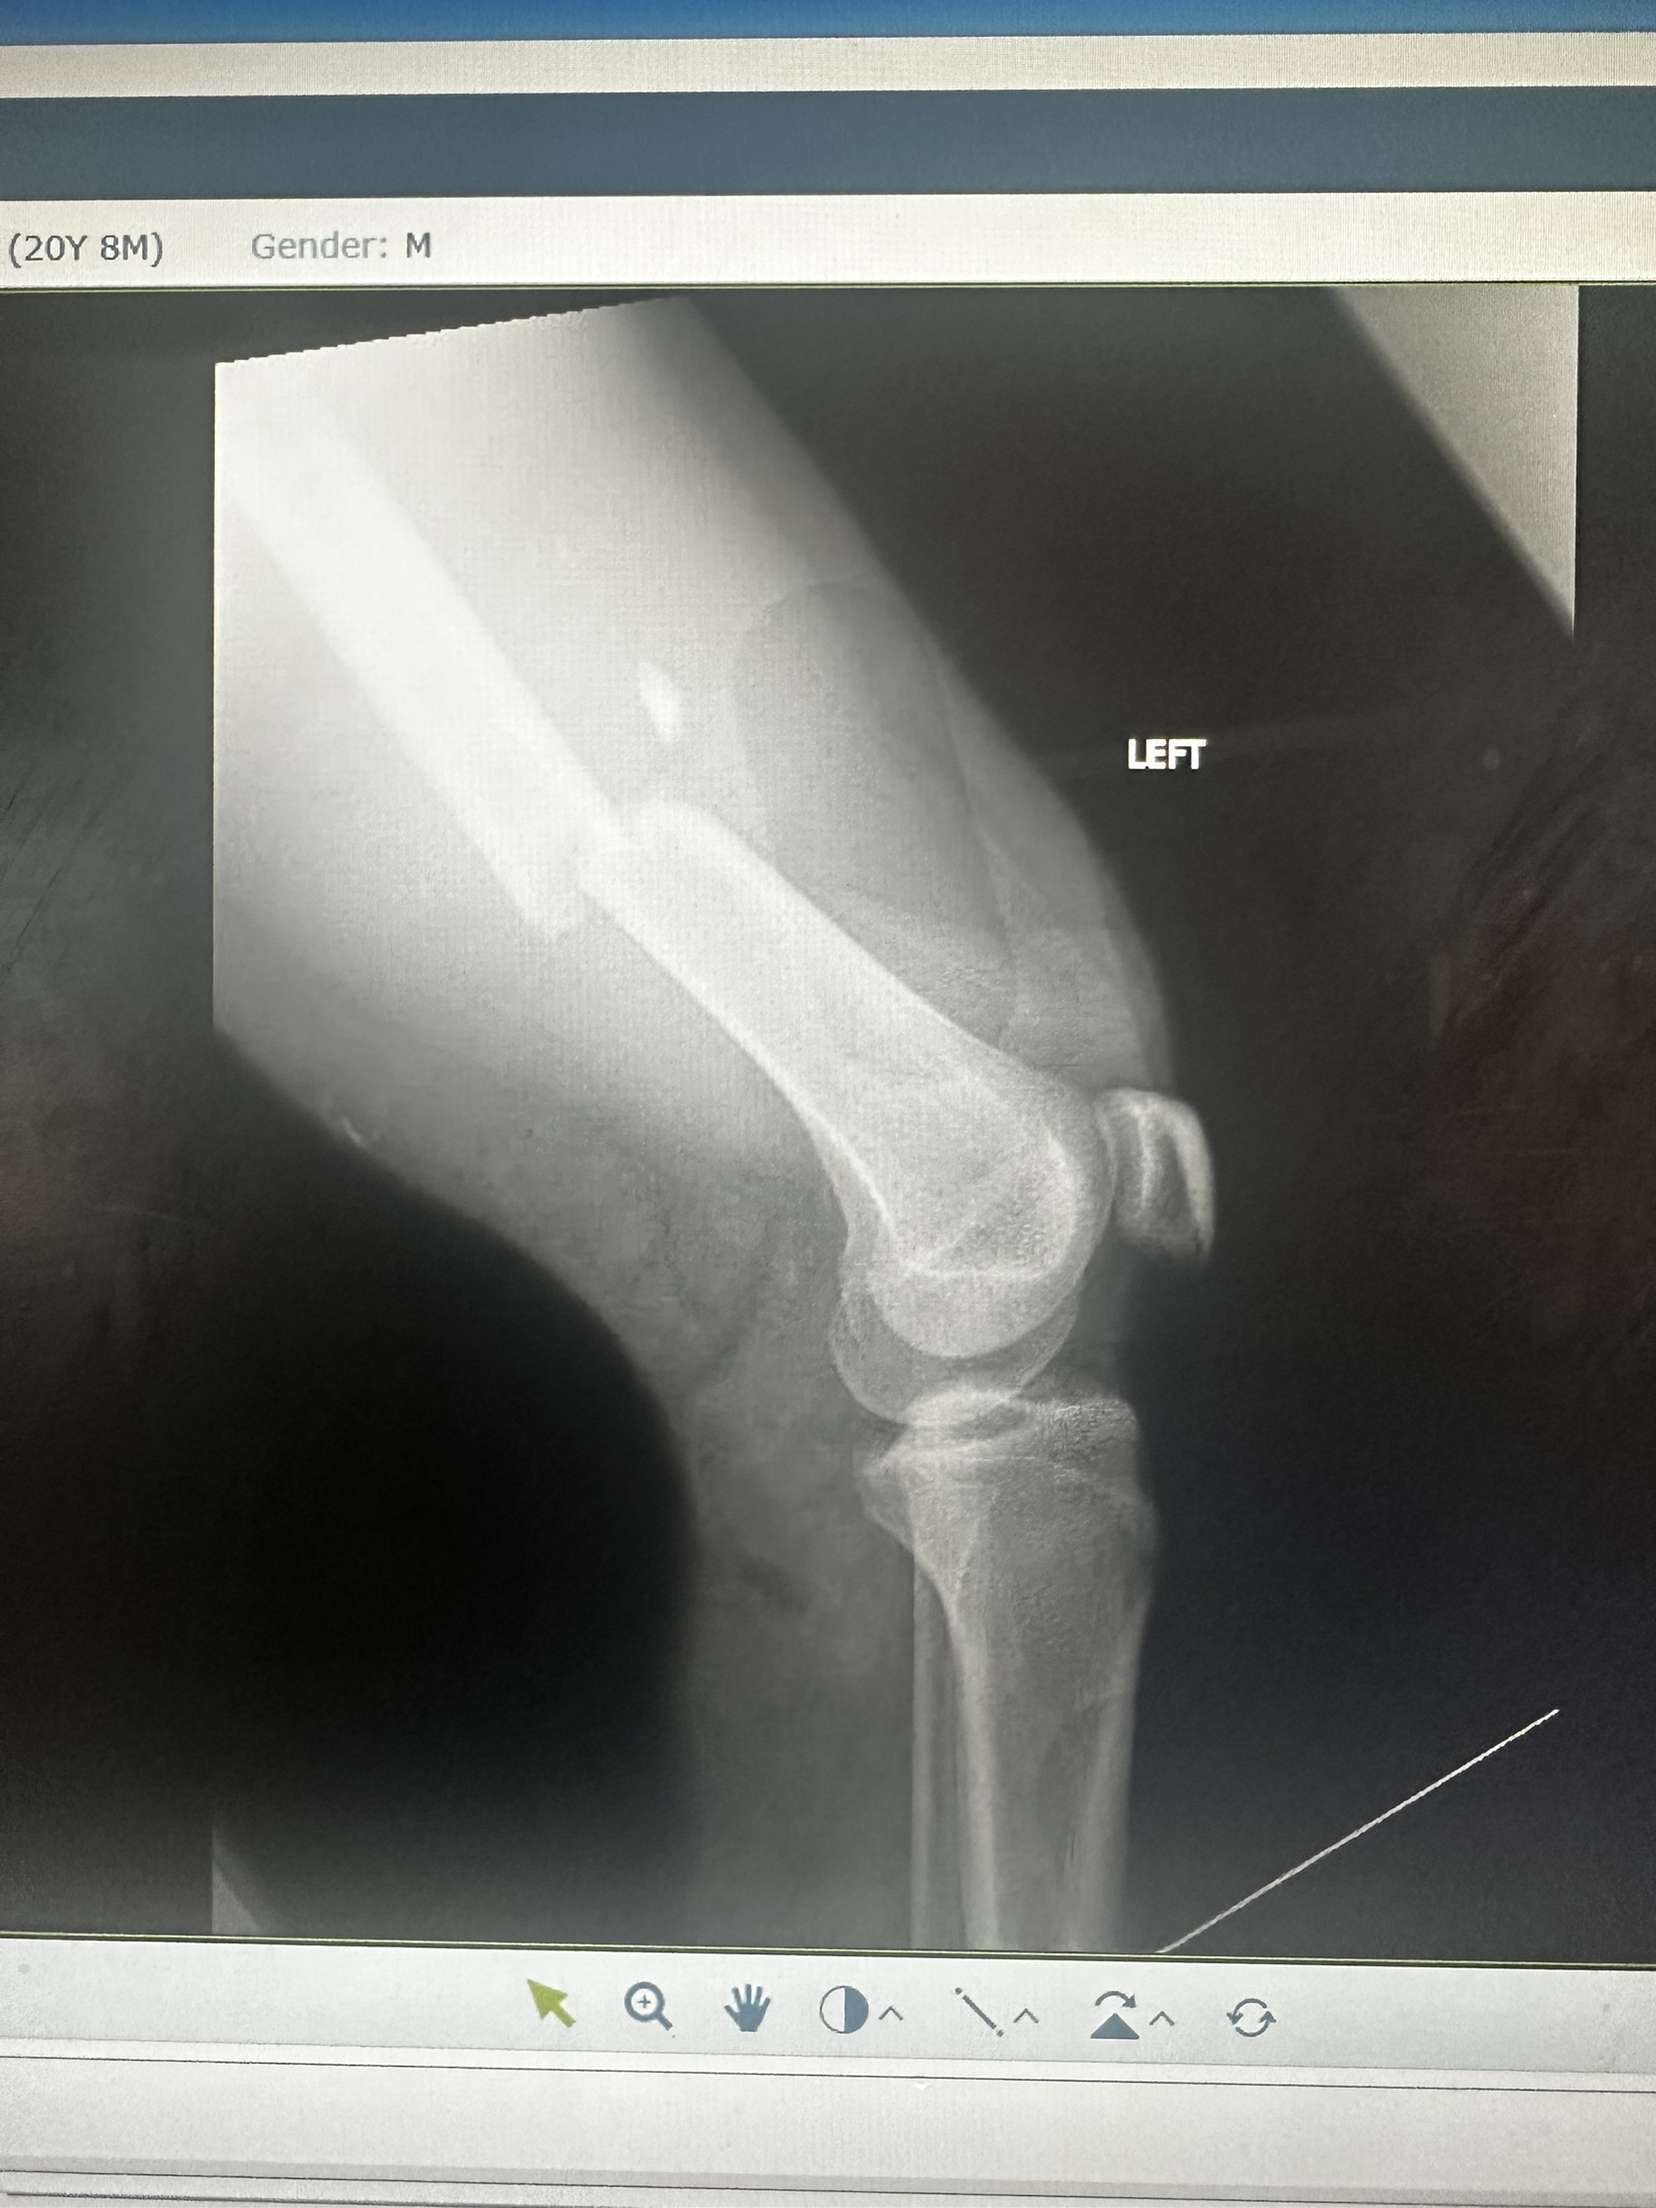

He broke his femur and tore femoral artery he also has a collapsed lung and surgery on his femur on Wednesday.